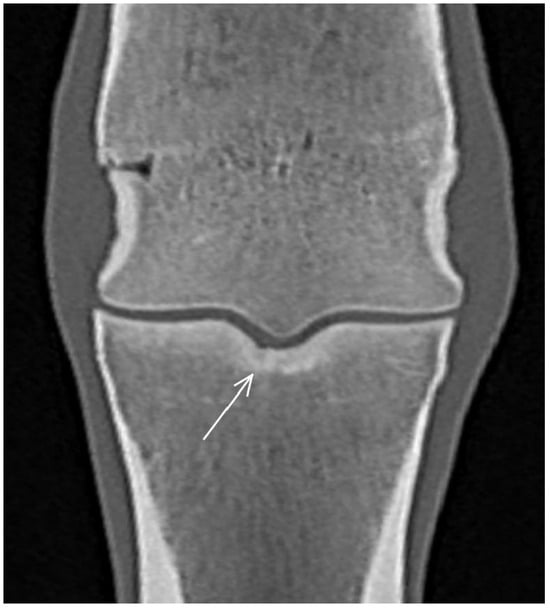

| Proximal phalanx Sagittal groove | |||

| Subchondral bone thickening Dorsal/middle/palmar third Increased attenuation in the trabecular bone Hypoattenuating lesion in the subchondral bone Location | Subchondral bone thickening Dorsal/middle/palmar third Decreased signal intensity in the trabecular bone Increased signal intensity in the subchondral bone Location | Subchondral bone thickening Increased opacity in the trabecular bone Lucent lesion in the subchondral bone Location | |

| Medial/lateral glenoid | |||

| Subchondral bone thickening Dorsal/middle/palmar third Increased attenuation in the trabecular bone Hypoattenuating lesion in the subchondral bone Location Periarticular modelling | Subchondral bone thickening Dorsal/middle/palmar third Decreased signal intensity in the trabecular bone Increased signal intensity in the subchondral bone Location Periarticular modelling | Subchondral bone thickening Increased opacity in the trabecular bone Lucent lesion in the subchondral bone Location Periarticular modelling | |